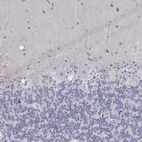

Immunohistochemical staining of human duodenum shows strong nuclear positivity in lymphoid cells.